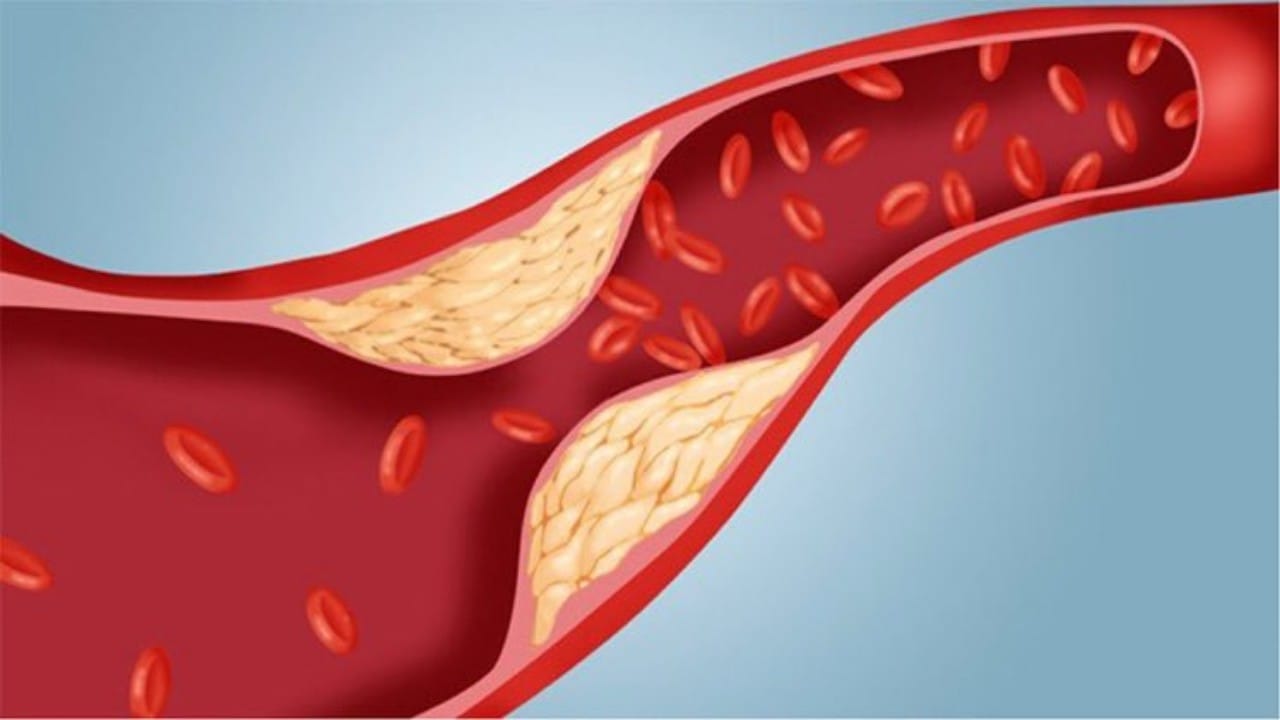

الذيابي يوجه نصيحة للمصابين بارتفاع دهون الدم

9 أسباب وراء الموت المفاجئ في مصر